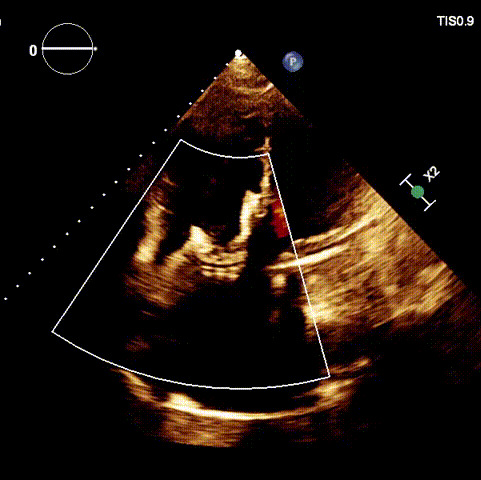

術前DSA

手術在全麻狀態(tài)下開展,海軍軍醫(yī)大學附屬長海醫(yī)院陸方林教授與廈門心血管病醫(yī)院王焱院長共同上臺,為患者進行手術。此次手術采用經(jīng)右側(cè)頸靜脈入路的方式將輸送器送入患者心臟內(nèi),在TEE及DSA引導下調(diào)整輸送器頭端角度,使得輸送器與三尖瓣瓣環(huán)平面垂直。在輸送器進入右心室后釋放室間隔錨定裝置,而后釋放瓣葉夾持件(2個耳片結(jié)構)成垂直狀態(tài)。在TEE及DSA確定夾持件固定至三尖瓣葉根部且位于右室側(cè)后釋放人工瓣心房側(cè)盤片。隨后調(diào)整瓣膜同軸性以及室間隔錨定件位置(貼合室間隔),前推藏針管并固定,進而釋放室間隔錨定裝置,并再次確認瓣膜位置、穩(wěn)定性及同軸性,合攏輸送鞘后撤出輸送器,完成LuX-Valve Plus人工三尖瓣瓣膜的植入。

術后DSA